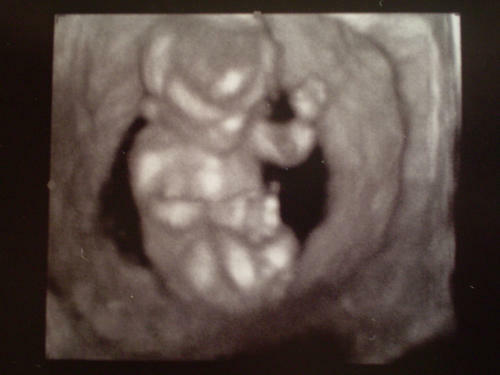

Cat! nagyon várjuk a híreket meg aképet!!!

biztos vagyokbenne hogy nagyon jó minőségű szépképet fogsz kapniés egybőlm rakd ide nekünk

egyből-egyből-egyből!!!

meg az uhu méreteket

tényleg majd én is felrakom améreteket. amire emlékszem hogy 30cmhosszú és 600gramm adrágám!!